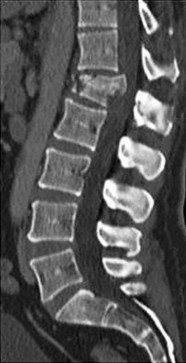

A 35-year-old male construction worker falls 10 feet from scaffolding. He complains of moderate low back pain but has full strength and normal sensation in his lower extremities.

CT imaging shows an L1 burst fracture with 40% loss of anterior vertebral body height and 50% retropulsion into the spinal canal. MRI confirms that the posterior ligamentous complex (PLC) is intact. Based on the Thoracolumbar Injury Classification and Severity (TLICS) score, what is the appropriate score and recommended management?

Question 25

A 35-year-old male is involved in a motor vehicle collision. Examination reveals normal motor and sensory function throughout his upper and lower extremities. CT imaging shows an L1 burst fracture with 15 degrees of local kyphosis and 30% canal compromise. MRI confirms an intact posterior ligamentous complex. According to the Thoracolumbar Injury Classification and Severity (TLICS) score, what is the indicated treatment?

A 35-year-old male falls from a ladder and sustains localized thoracolumbar pain. He is neurologically intact. CT and MRI confirm an L1 burst fracture with 15 degrees of kyphosis, 30% canal compromise, and an intact posterior ligamentous complex.

Based on the Thoracolumbar Injury Classification and Severity (TLICS) score, what is the most appropriate management?